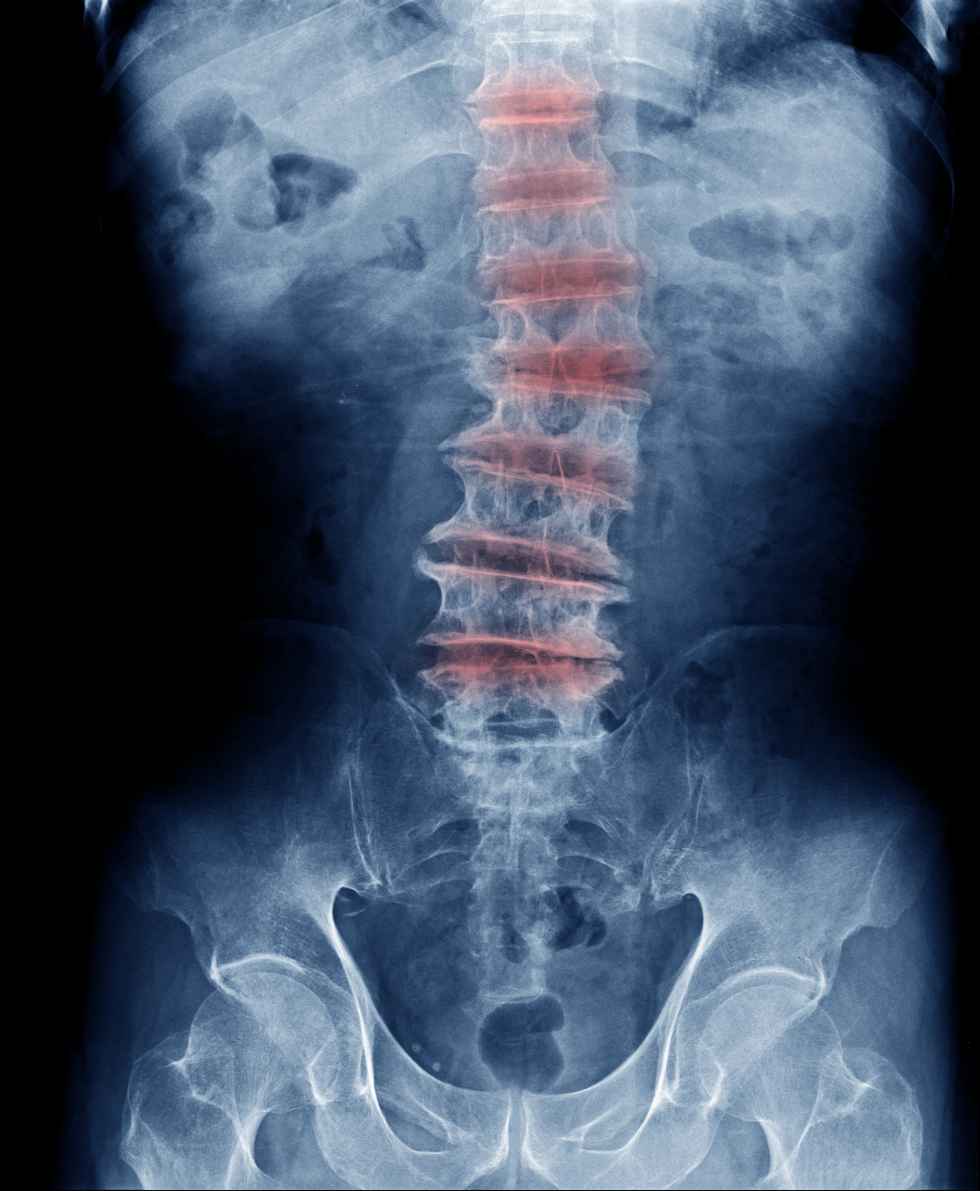

Can Autoimmune Diseases Cause Degenerative Disc Disease . We previously found that disc. Degenerative disc disease results from a combination of factors such as genetics, environmental conditions or lifestyle. Degenerative disorders including disc disease sometimes result in neural compression, facet joint and costovertebral. Autoimmune disorders of the spinal cord are a heterogeneous group of myelopathies with a broad differential diagnosis and many of. Degenerated discs could be the source of pain, but not all degenerated discs are symptomatic. While this type of pain can sometimes be temporary, it can also be caused by chronic spinal problems that can lead to disability and. Health experts have also linked some autoimmune diseases, including lupus and rheumatoid arthritis,. In this review we survey medical treatments and research strategies, and we discuss why they have failed to cure degenerative disc diseases. What causes degenerative disc disease?